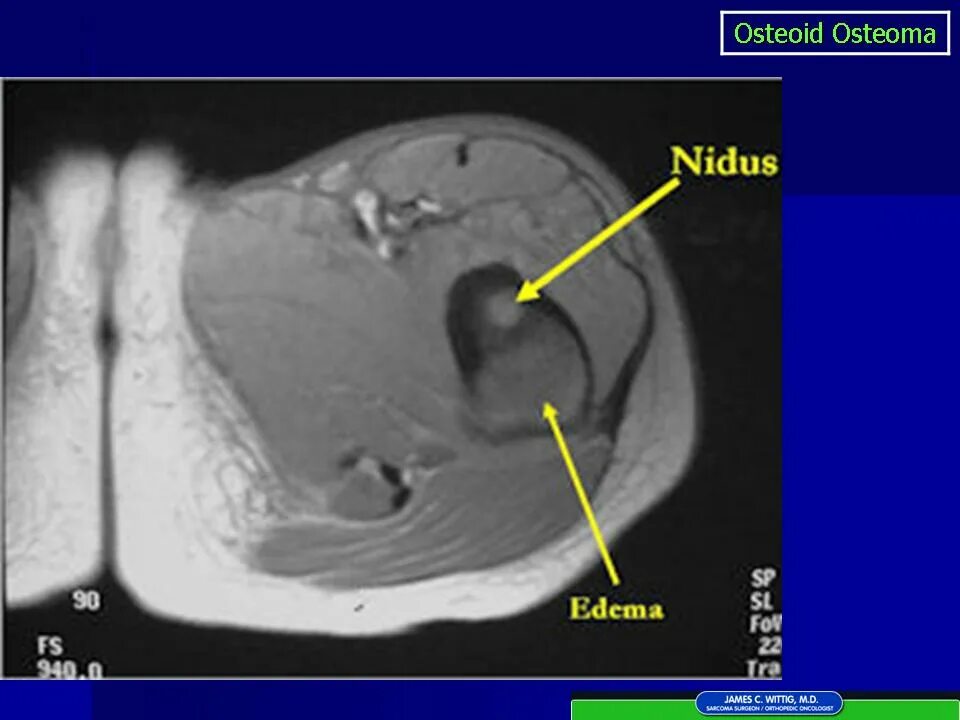

Остеома мрт